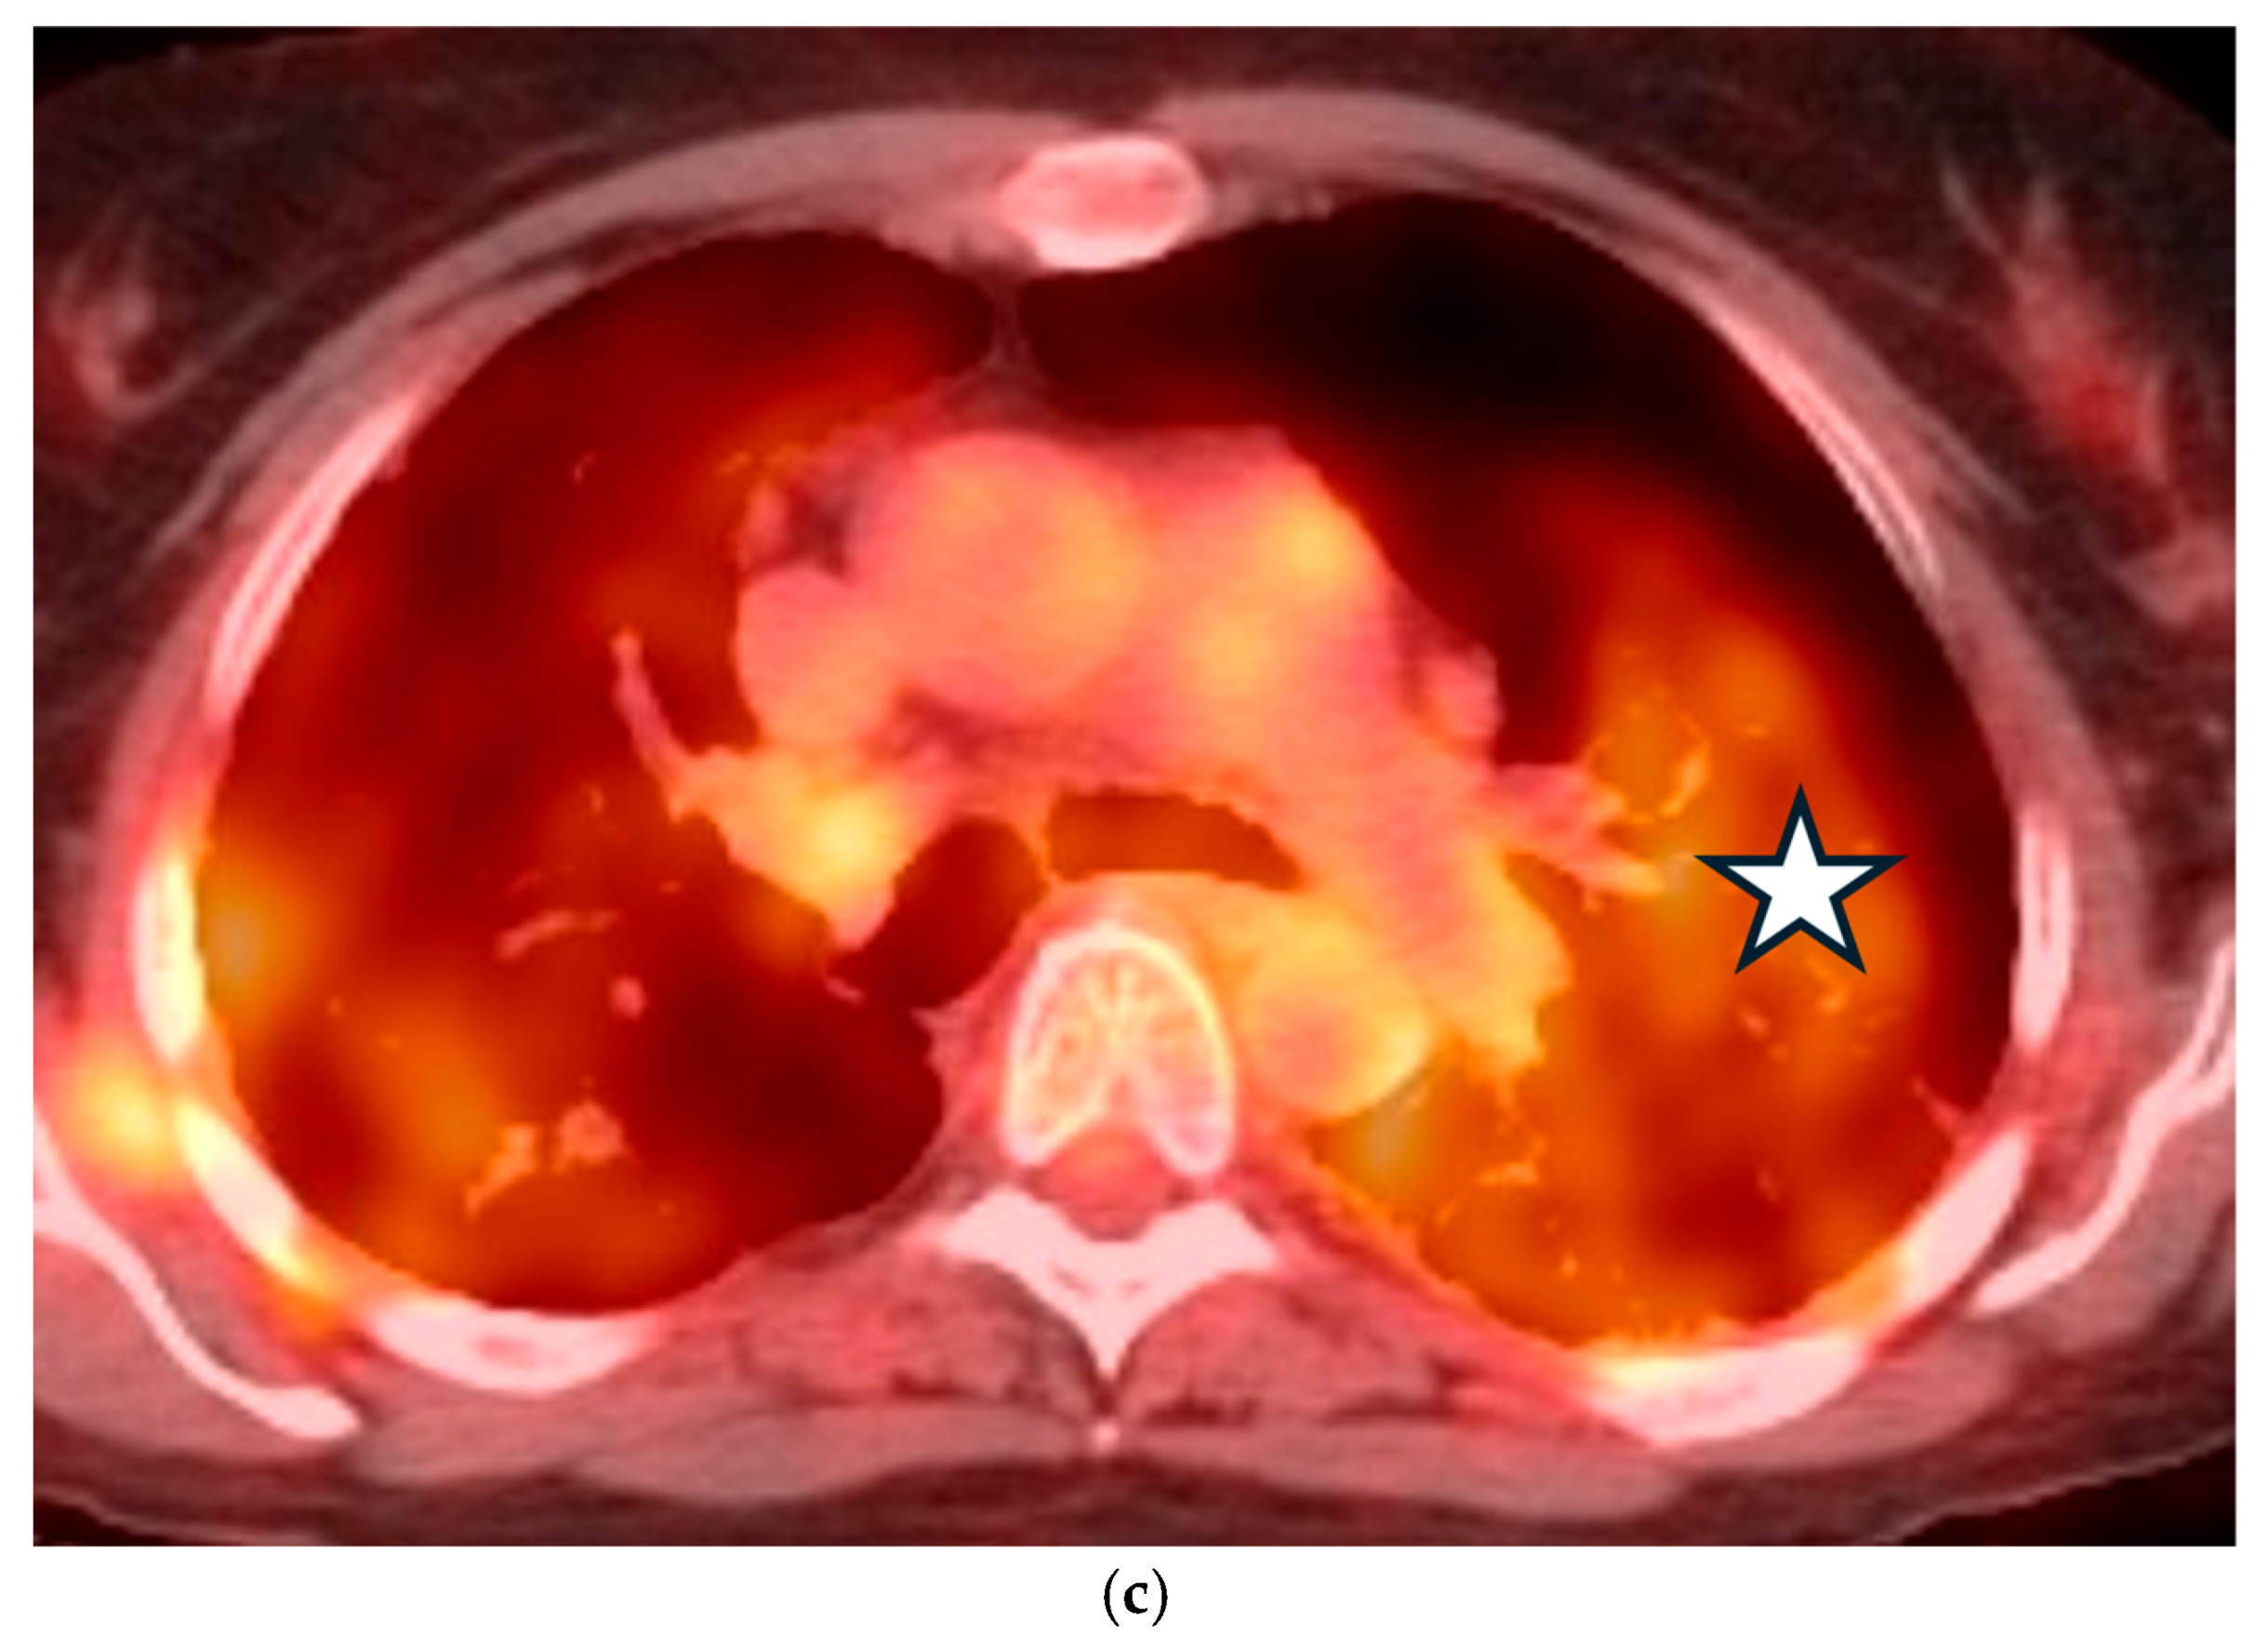

5.3. Malignancies

5.4. Interstitial Lung Diseases (ILDs)